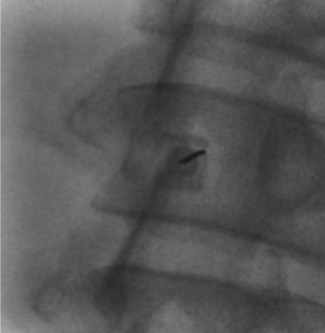

Fluoroscopic approach views

AP fluoroscopic view showing midline approach for lumbar puncture Prone oblique fluoroscopic view showing paramedian approach for lumbar puncture Second prone oblique view showing needle trajectory for lumbar puncture

Midline approach: Advance the spinal needle between the spinous processes, through the supraspinous ligament, interspinous ligament, and ligamentum flavum. Keep the hub directly over the tip on fluoroscopy to eliminate parallax. Feel for the characteristic "pop" through the ligamentum flavum. Remove the stylet to check for CSF flow.

Oblique/paramedian approach: The needle enters lateral to the spinous processes and is directed toward the interlaminar space ("behind the Scotty dog's neck" on oblique fluoroscopy). This avoids the strong midline ligaments and calcified bridging osteophytes in patients with degenerative disease. May be more comfortable for the patient.